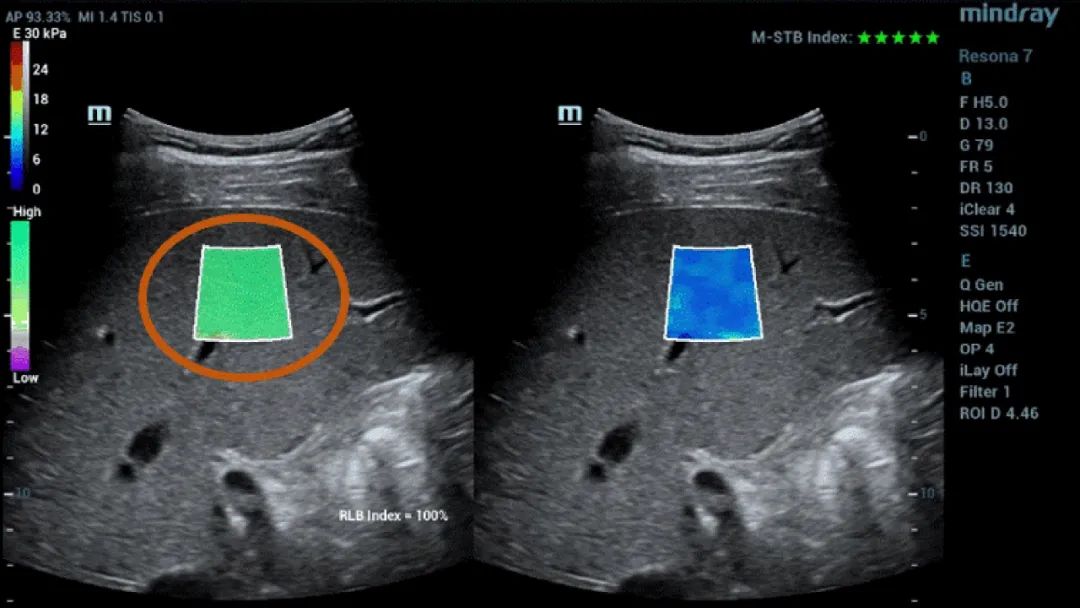

Рисунок 1 (продолжение): (e) Изображения, полученные с помощью 2D SWE (STE; Mindray, Шэньчжэнь, Китай). Приводятся два критерия качества: индекс стабильности (M-STB), отображаемый звездочками (наибольшая стабильность- пять звездочек зеленого цвета), и карта надежности (RLB), с цветами от фиолетового до зеленого - последний означает высокую надежность. Звездочки являются индикатором движения во время получения данных. Если количество отображаемых звездочек менее четырех, значит, во время получения данных наблюдается значительное движение, и этот кадр не следует использовать для измерения жесткости ткани печени. (f) Полученные изображения

Таким образом, технология Sound Touch Elastography (STE) компании Mindray обеспечивает высокую надежность результатов измерений, получаемых во время исследования с помощью 2D-эластографии сдвиговой волной, благодаря коэффициентам качества и достоверности, включая индекс стабильности (M-STB), карту надежности (RLB), индекс надежности (RLB), и т. д.

Индекс M-STB указывает на наличие/степень помех, вызванных дыханием пациента или движениями оператора. Индикатор представлен в виде звездочек (наибольшая стабильность- пять звездочек зеленого цвета), надежное изображение должно иметь ≧4 зеленых звездочки.

Карта RLB указывает на надежность изображений STE, ее цвет меняется от фиолетового к зеленому, последний указывает на высокую надежность. При коэффициенте RLB ≧90% изображение является надежным.